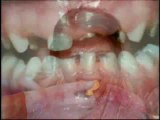

Dr Shoaib Khan | Dental Clinic | Audeo Concepts Production

Dr.Shoaib Khan Dental Clinic | Audeo Concepts Production <br /> <br />Director | Producer: kamijee